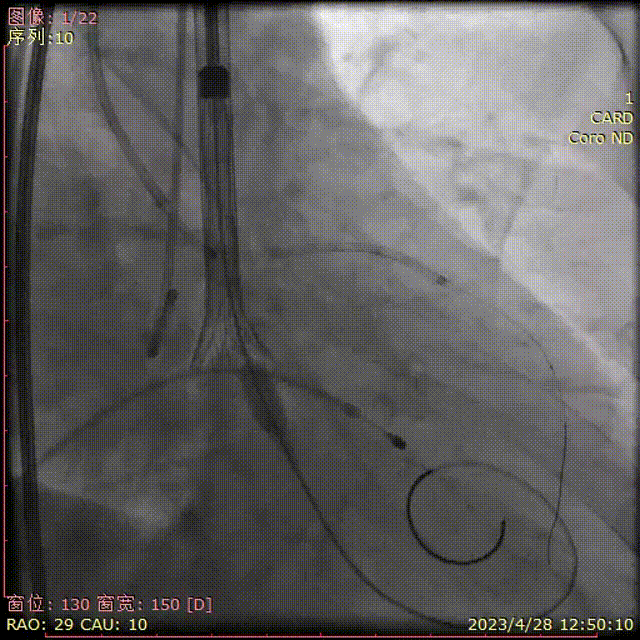

完全释放后评估,位置理想,冠脉灌注正常

释放后超声评估

释放后超声下多切面评估,瓣膜位置可,无明显瓣周漏

测得主动脉瓣流速由5.4m/s改善至1.9m/s